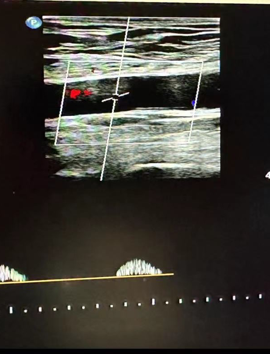

心功能室的李月醫(yī)生在檢查時敏銳捕捉到異常信號:雙側(cè)股總動脈血流頻譜呈特征性“小慢波”——這通常是大血管嚴重狹窄的強烈提示。

然而,蹊蹺之處隨之浮現(xiàn)。醫(yī)生仔細掃查了患者從股動脈直至腹主動脈的整條下肢供血通路,血管結(jié)構(gòu)清晰,未見明顯狹窄或斑塊。

經(jīng)驗豐富的醫(yī)生判斷問題可能潛藏在更近心端的胸主動脈,但該區(qū)域受胸骨遮擋,常規(guī)超聲探查受限。

心功能室王璇主任會診后,結(jié)合異常血流動力學特點,將目標鎖定超聲探查難點——胸骨遮擋的降主動脈胸段!建議行主動脈CT血管成像(CTA)檢查以明確診斷。

CTA結(jié)果印證了王璇主任的判斷:患者降主動脈胸段(距鎖骨下動脈約10厘米處)存在一處少見的先天性局部縮窄,并伴有遠端擴張。這正是導致患者下肢血流灌注不足、多年感覺發(fā)涼的“元兇”——降主動脈縮窄,一種少見的血管發(fā)育畸形!